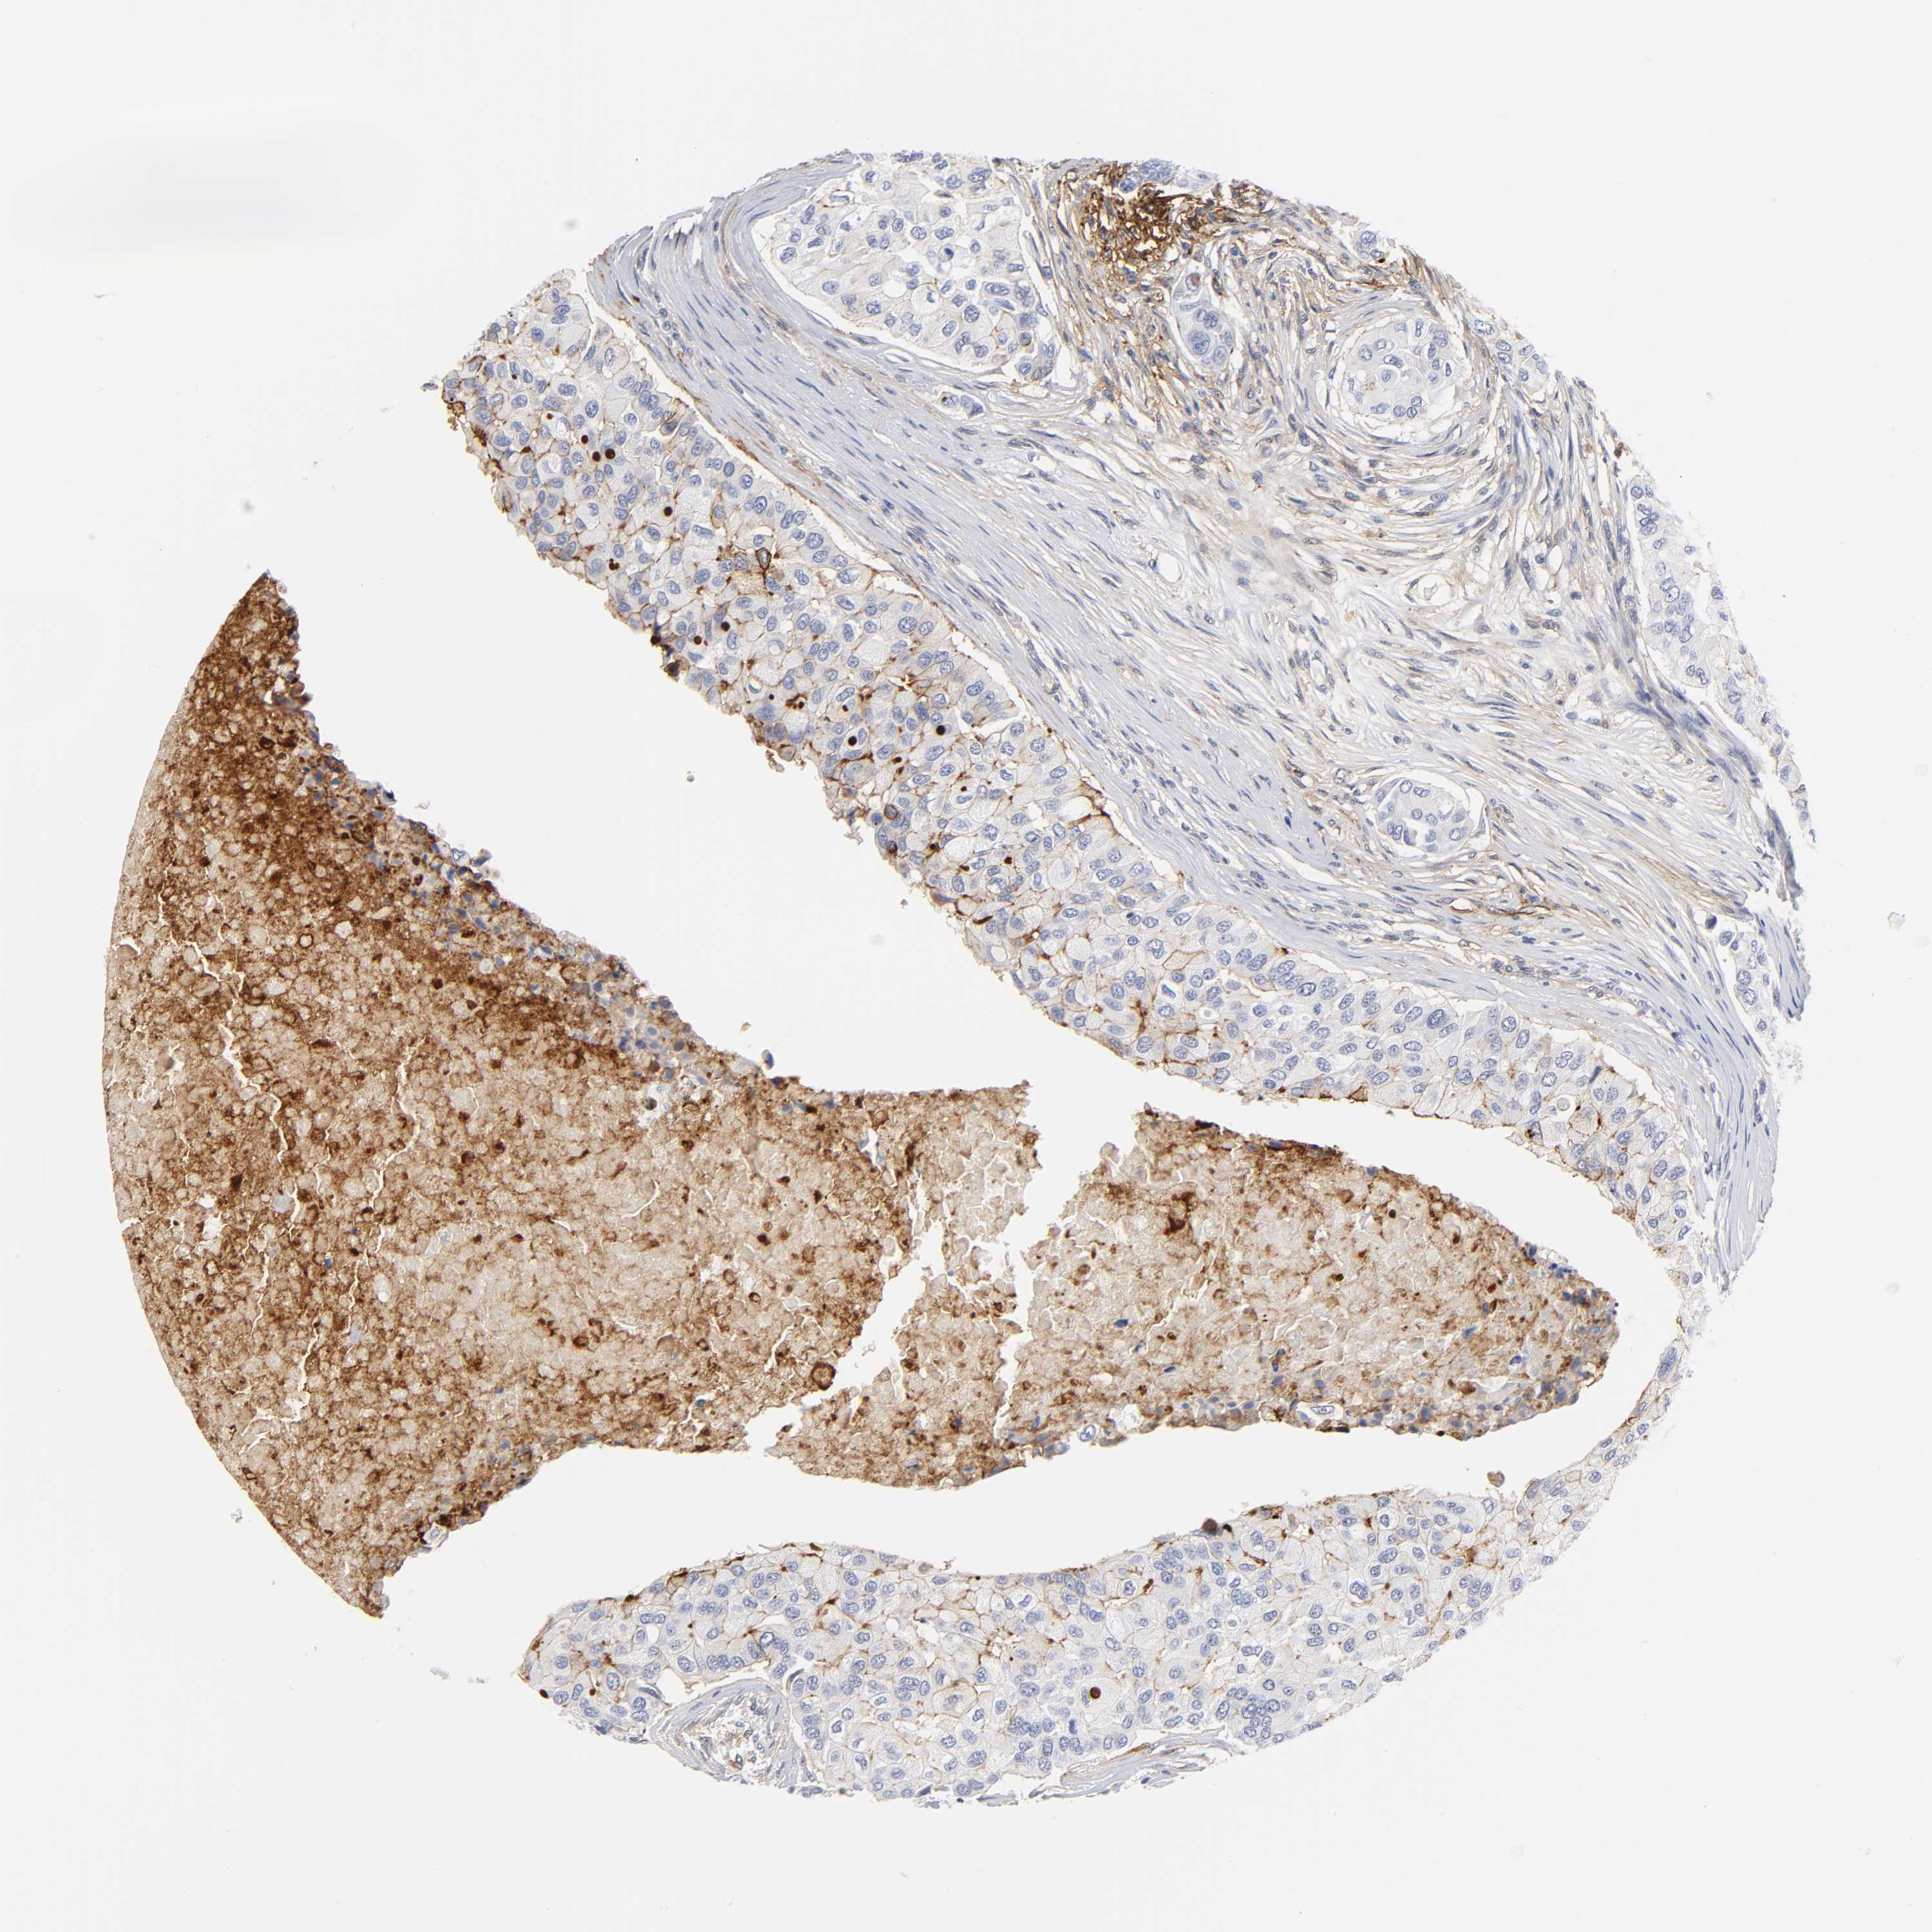

BRCA TCGA BRCA VALIDATION PROTEIN EXPRESSION

ANTIBODIES

AND

VALIDATION